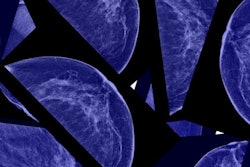

Contrast-enhanced mammography (CEM) and contrast-enhanced MRI (CE-MRI) show comparable performance when it comes to identifying breast cancer, but CE-MRI is more sensitive, a study published on 7 June in Radiology has found.

Mammography is the go-to modality for breast cancer screening, but it has sensitivity limitations in dense tissue. Digital breast tomosynthesis (DBT) and ultrasound are useful adjunct breast screening modalities, but breast MRI -- particularly contrast-enhanced exams -- is the most sensitive imaging tool for women with dense tissue, the authors explained.